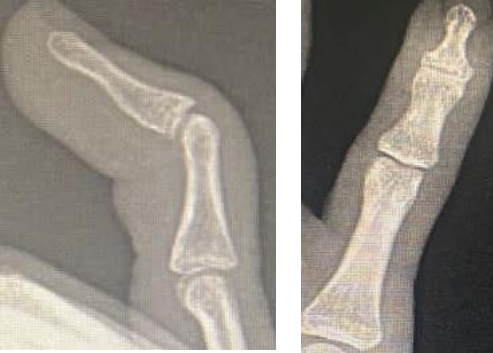

Patient presented to the outpatient department of our hospital with a mallet deformity of fifth finger of the right hand. On examination, he was found to have a mallet deformity (figure 1a and 1b) with an extensor lag of 40 degrees which was bothering him.

Fig: 1a, Fig: 1b

Mallet deformity of the fifth finger right hand

He had further flexion from the existing flexion deformity of DIP joint and no active extension was possible.

The deformity was passively correctable, the patient was found to have a mild Swan-neck deformity in the finger was noted, but it was equivocal in both hands. Radiological assessment revealed a tendon mallet injury without any bony involvement (figure 2a and 2b).